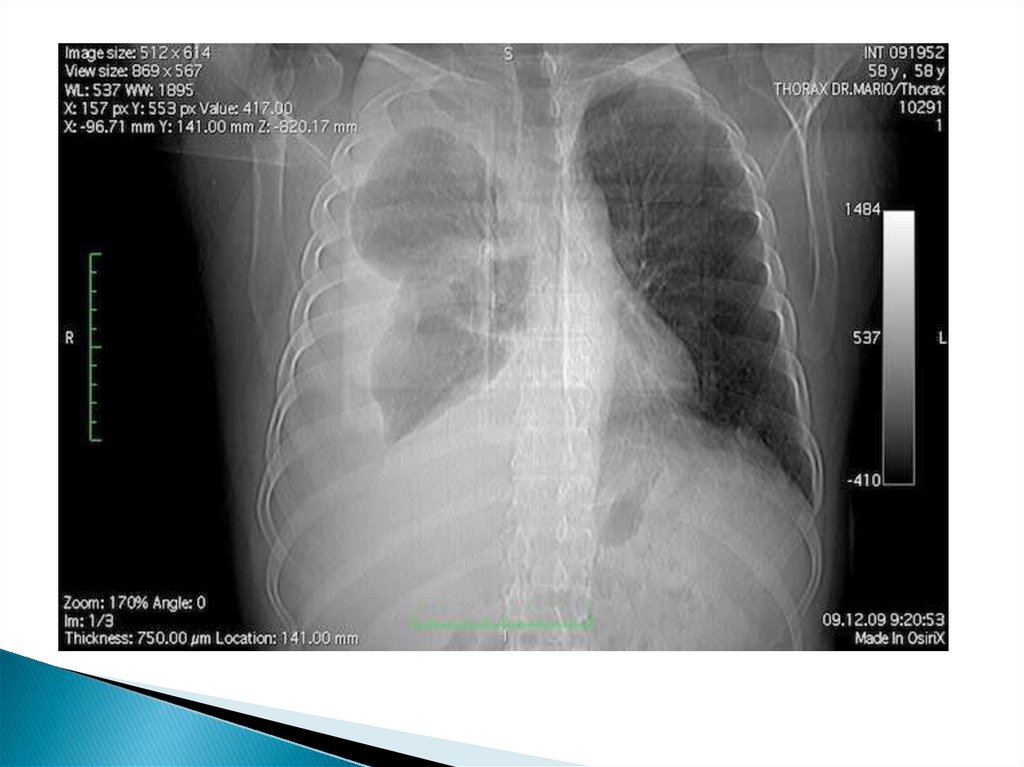

Рентгенограмма органов грудной клетки. Правосторонний экссудативный плеврит туберкулезной этиологии.

Основные причины возникновения плевритов при злокачественных новообразованиях:

12. Рентгенограмма органов грудной клетки. Правосторонний экссудативный плеврит туберкулезной этиологии.

13.

Рентгенограмма

органов грудной

клетки.

Правосторонний

экссудативный

плеврит

туберкулезной

этиологии.

14.